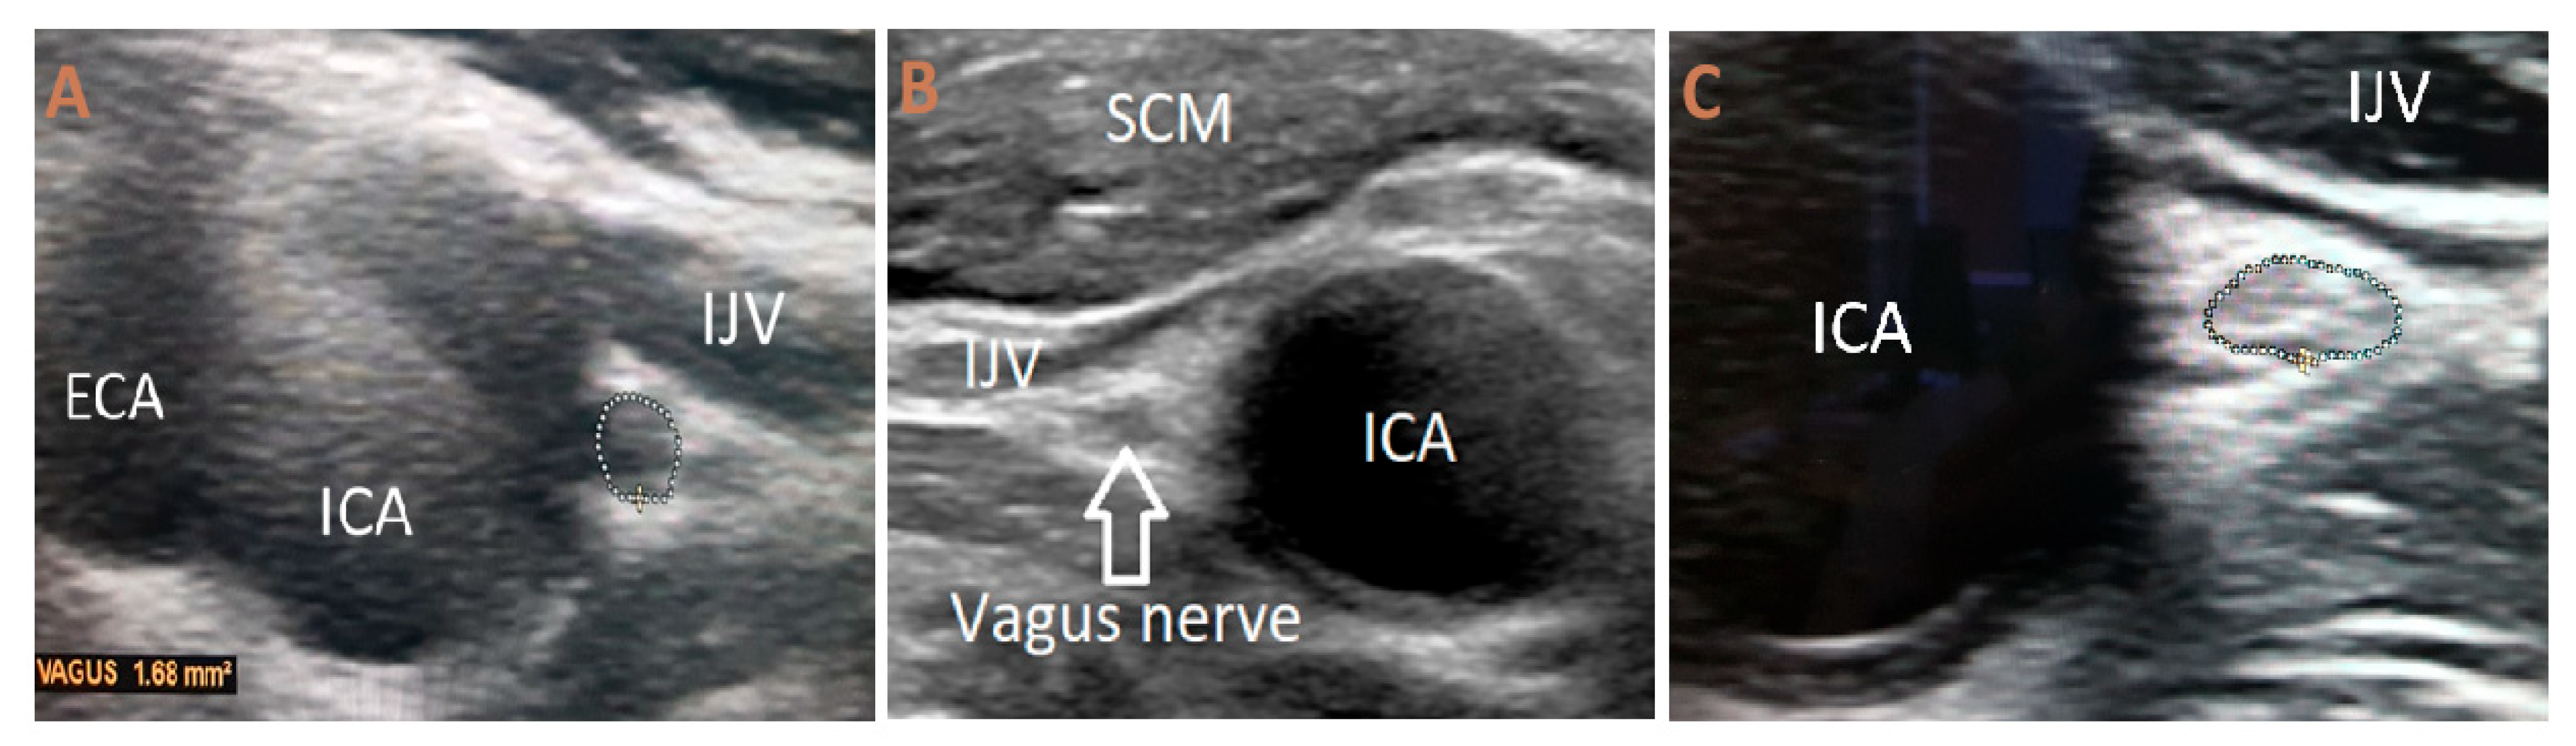

Measurements of the nerve’s diameter were obtained in millimeters from transverse images at two distinct sites: in the vicinity of the carotid bulb and at the level of the common carotid artery bifurcation. Both morphometric and qualitative characteristics were documented. The internal echotexture was described as either uniform or non-uniform, and echogenicity was categorized as hypoechoic, isoechoic, or hyperechoic (Figure 1).

Figure 1. (A) Ultrasonography of the vagus nerve (USVN) showing a hypoechoic and homogeneous structure in a healthy volunteer. (B) USVN of a PD patient demonstrating an isoechoic and homogeneous appearance (C) USVN of a PD patient, demonstrating a hyperechoic and heterogenous appearance. The dotted circle indicates the cross-sectional area of the vagus nerve. SCM—sternocleidomastoid muscle; IJV—internal jugular vein; ICA—internal carotid artery; ECA—external carotid artery.